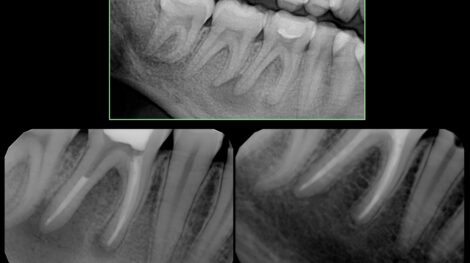

Gojenie zmiany w bifurkacji